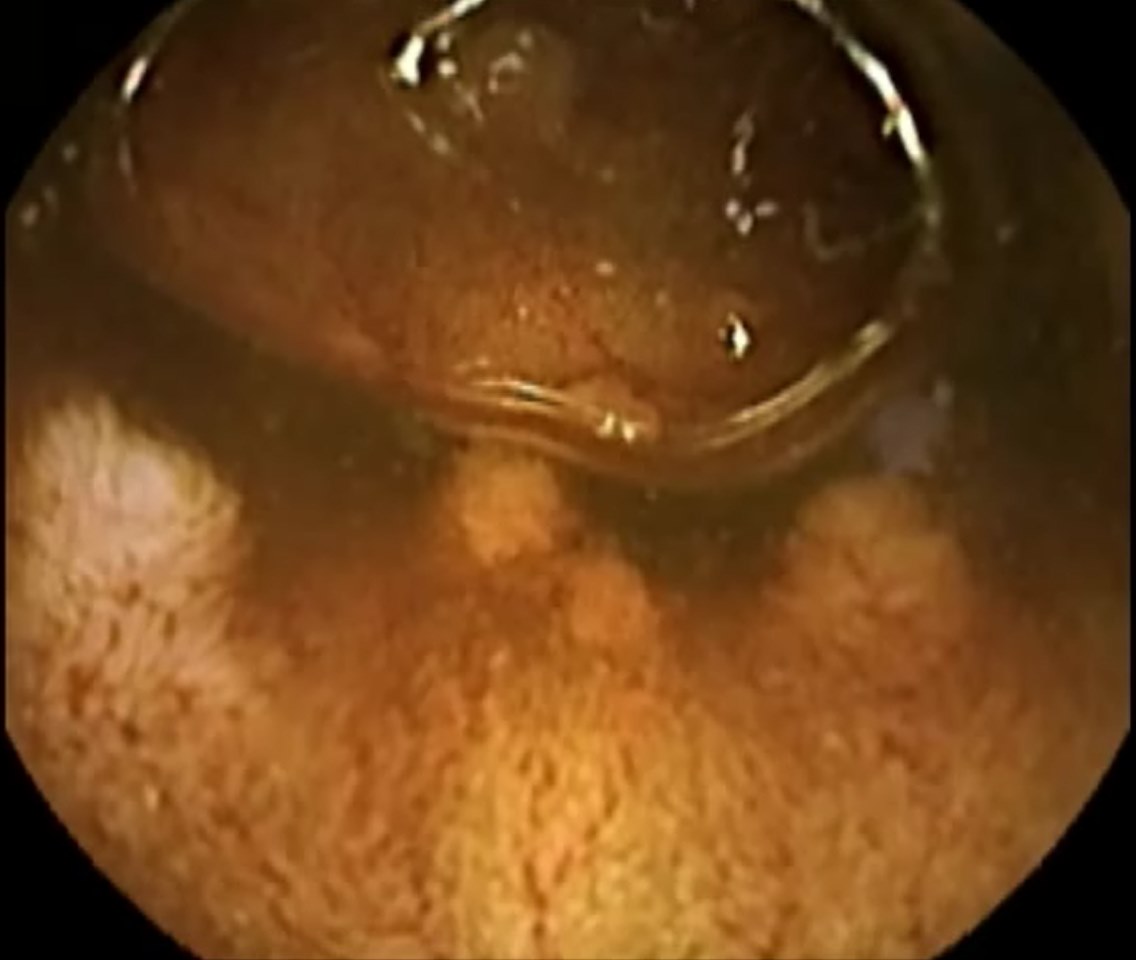

Capsule Endoscopy: Ileum Terminale, Lymphoid Hyperplasia

Capsule Endoscopy: Ileum Terminale, Lymphoid Hyperplasia. Just click on a picture!